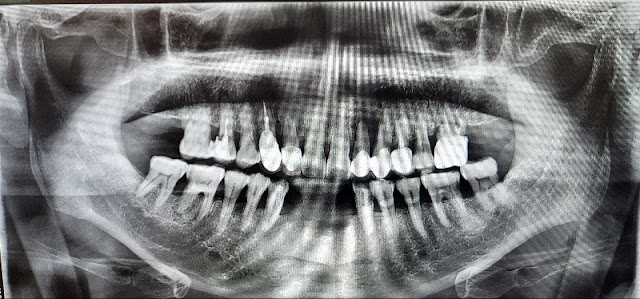

4th mandibular incision case

This is the 4th mandibular incision.

This is a case where the patient does not have high aesthetic demands and is therefore satisfied.